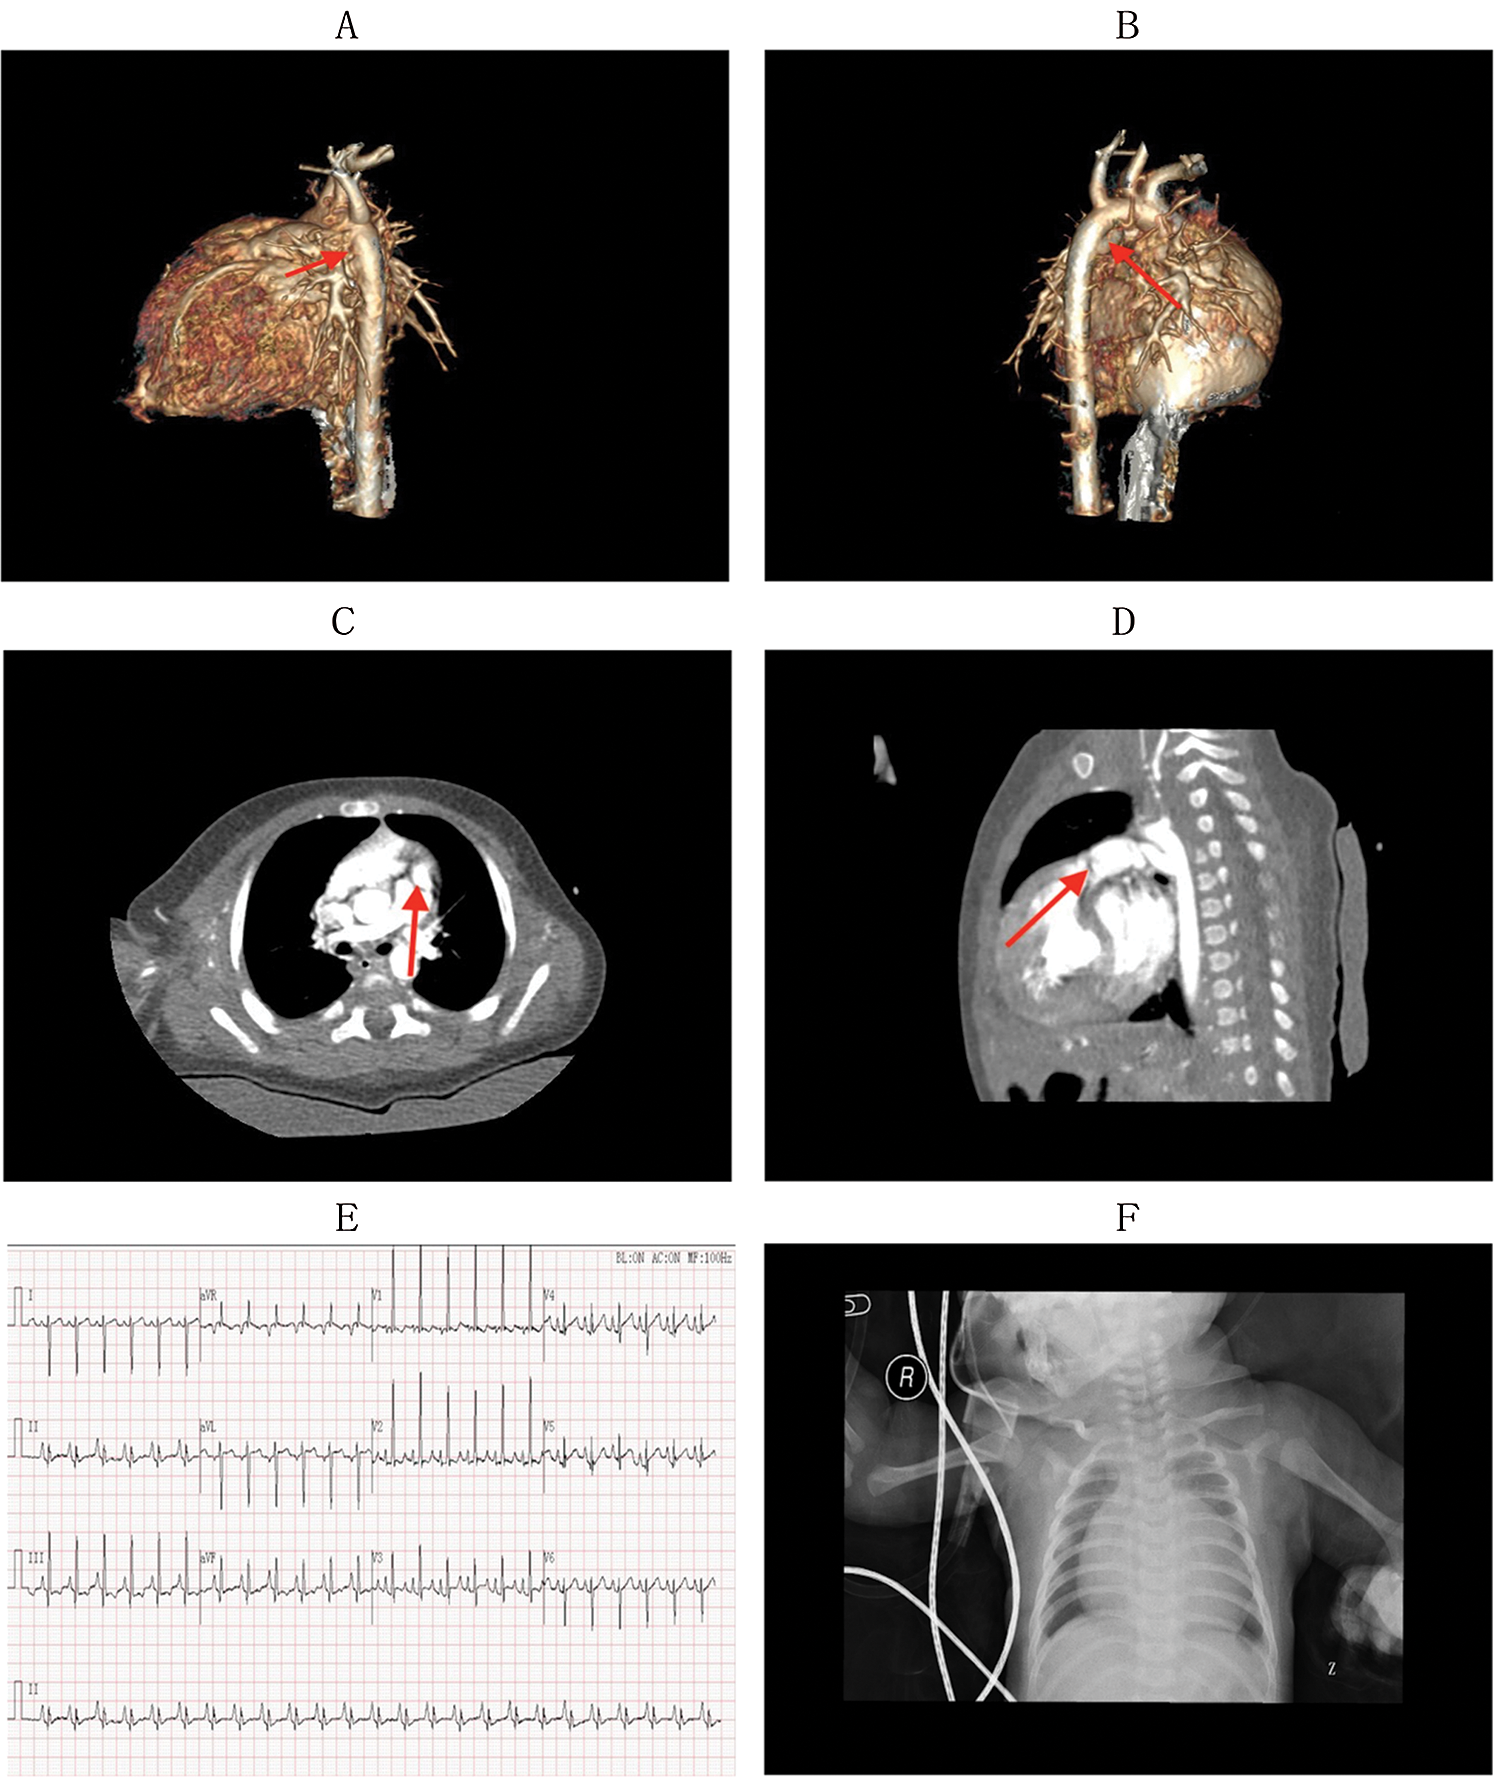

Physical examination and imaging assessment were performed by two cardiothoracic surgeons and two imaging specialists in our hospital. Physical examination revealed cyanosis, wheezing, and shortness of breath, and continuous murmurs could be caught on the precordium. The relevant auxiliary examinations before surgery, including CT scan, electrocardiogram, and chest radiography, are presented in Fig. 2. After obtaining written consent and signatures from all participants or their legal guardians, venous blood was collected from six people in the family. The collection and use of patient biological samples was reviewed by the Shanghai Children’s Hospital Ethics Committee (No. 2019R001-E01).

Figure 2: The relevant auxiliary examinations before surgery: CT scan, electrocardiogram, and X-ray of chest

Panels A–D show the CT scan before surgery (A: red arrow shows a narrow pulmonary artery of the proband; B: the red arrow shows the blood supply of the pulmonary artery was the descending aorta; C, D both show pulmonary atresia as well as an undeveloped pulmonary valve). Panel E shows the electrocardiogram of the proband before surgery, which presents an atrial hypertrophy, ventricular hypertrophy, change in ST and T waves. Panel F shows the X-ray of the chest of the proband before surgery, which presents an increased heart shadow. The cardiothoracic ratio of the proband was approximately 75.9%.